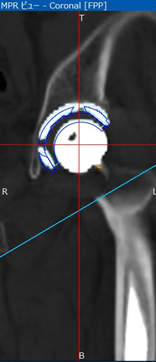

- 術後1週のCTデータをZedHipに取り込む

- 術後評価機能を用いて設置角度評価

RI, RA, SA

- 術前計画機能を用いて再度術後ROM simを施行

計測肢位: ①屈曲120度②屈曲90内転20内旋30度③内転10外旋30度④伸展30度インピンジメント: 角度 (①と④で最大値を評価)様式 インプラント同士: I-I impインプラントと骨: B-I imp骨と骨: B-B imp

ZedHip による3次元術後評価の実際

①術後評価機能を用いて設置角度評価

![]() |

| 図1: 術前骨モデルと術後MPR画像を自動マッチング | 図2: 計画インプラントCADデータを誤差分移動 青線:術前計画 白色:実際のカップ 水色線:CADデータ輪郭 |

図3: 術前計画との差が自動表示 |